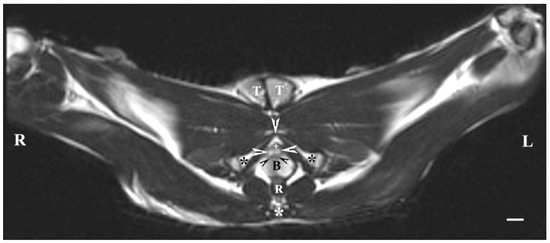

The dorsal imaging of the pelvic findings was on T2-weighted sequences but at the closest distance to the pelvic symphysis, which demonstrated the ventral parts of the bulbourethral glands located on the lateral wall of the pelvic urethra. The latter were relatively hyperintense, homogeneous, with elongated craniocaudally soft tissue structures, compared to the vesicular glands and the prostate glandular complex. The pelvic urethra was hypo-intense compared to the ventral parts of the bulbourethral glands, prostate complex and vesicular glands. The shape of the ventral parts of the bulbourethral glands was craniocaudally elongated and oval, with poorly defined borders (capsule). The glandular finding was visualized as a compacted, thickened and hyper-intense part of the urethral wall (Figure 6).

Figure 6. T2-weighted dorsal image of rabbit pelvis (at the level, close to the pelvic symphysis): R—right; L—left; CR-cranial; CD—caudal. Bulbourethral glands (horizontal white arrows), prostate complex (P), vesicular glands (white cross), pelvic symphysis (S), neck of the urinary bladder (V), the pelvic part of the urethra (white star), urinary bladder (U), adipose tissue (A). Line—10 mm.

The T2-weighted dorsal image of the bulbourethral glands at the pelvic symphysis demonstrated the ventral portions of the glandular findings to be hyper-intense and homogeneous compared to the cranially located ventrocaudal parts of the prostate complex and pelvic urethra. The glands were presented as tissue-defined, irregularly oval perineal structures located at the caudal end of the pelvic urethra and cranially from the beginning of the penis. The studied glands were found in the central part of the perineum, with a characteristic intensity that could distinguish them significantly from the close soft tissues in the perineal region (Figure 7).

Figure 7. T2-weighted dorsal image of rabbit pelvis (at a greater distance, at the level to the pelvic symphysis): R—right; L—left; CR—cranial; CD—caudal. Bulbourethral glands (black stars), caudal part of the prostate gland complex (white horizontal arrows), the pelvic part of the urethra (white star), urinary bladder (U), and penis (P). Line—10 mm.